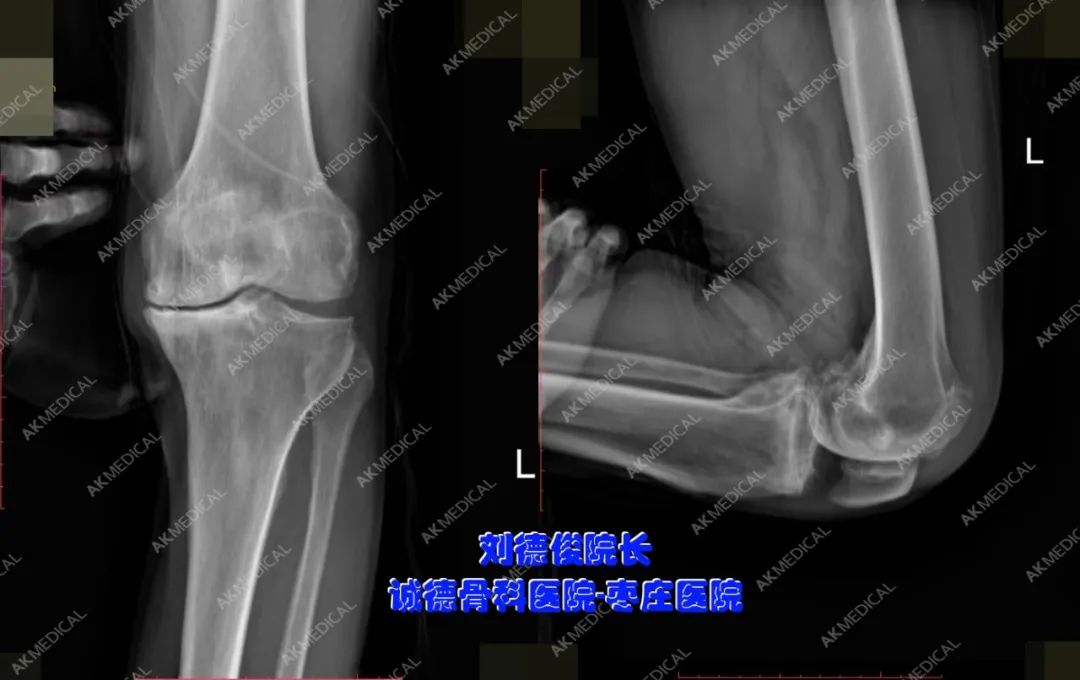

左側(cè)膝關(guān)節(jié)術(shù)前正側(cè)位X光片

左側(cè)膝關(guān)節(jié)術(shù)后正側(cè)位X光片